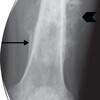

What are the key features shown in this x-ray?

Osteosarcoma Ill-defined mixed sclerotic/lytic lesions Periosteal reaction Cortical destruction Periosteal lifting - codmans triangle